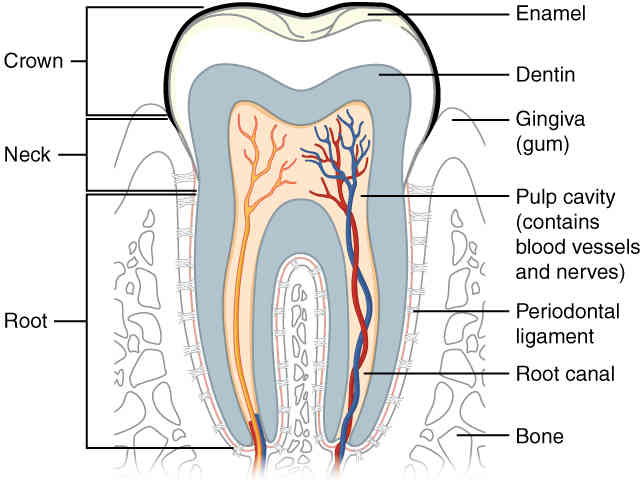

This page is under construction. For now, it is just a resource of the images found in the OpenStax Anatomy and Physiology Handbook. It wil slowly change into a revision tool. Each slide has a number. Use this to refer to the slide. When completed, it will have an unlabelled section, with labelled slides in parallel. On the unlabelled slides, write your answer and use the labelled slide to assess yourself. Keep track by also noting the number on each slide. Improvement at each attempt is important, more so than full marks on a first attempt.